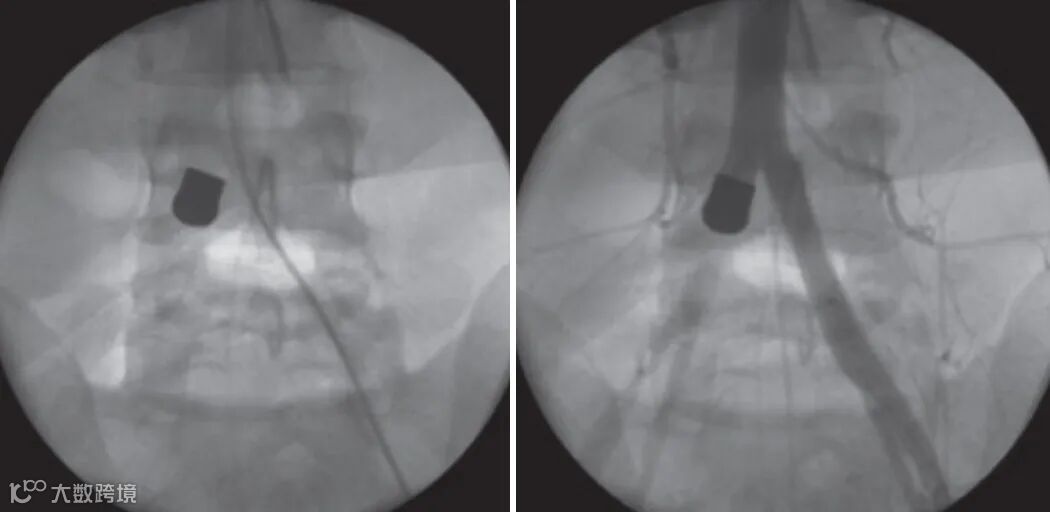

男,30岁,枪击伤口入口位于左侧第四肋间隙处,无出口伤。患者随后出现右下肢缺血征象。 术中血管造影显示弹丸头部栓塞至右髂动脉。